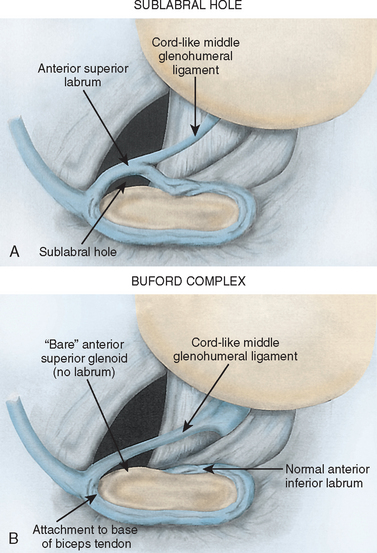

Glenohumeral ligament: анатомия и функции плечевого сустава